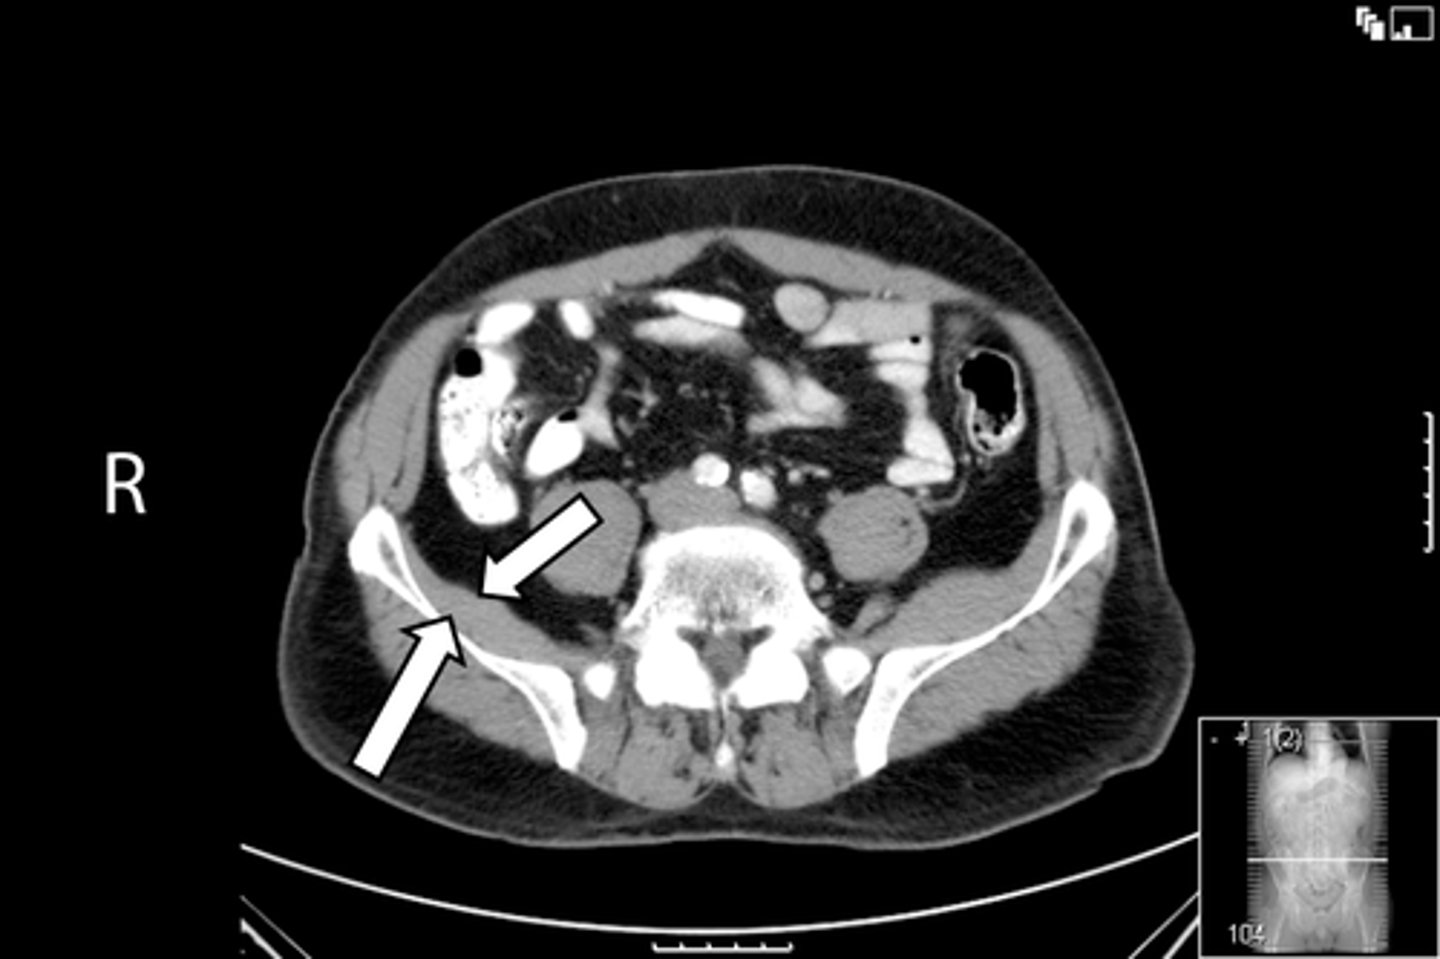

Axial bony pelvis CT

What is the image?

38

L acetabulum

What is indicated in the image?

<p>What is indicated in the image?</p>

39

New cards

L femoral head

40

L piriformis muscle

41

R femoral head

42

R piriformis muscle

43

R acetabulum (posterior part)

44

Sacrum